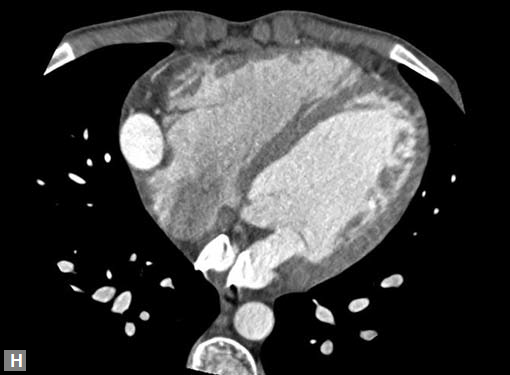

Connective tissue disease, hypertension and iatrogenic (Figs 19K to L) injury are the common causes for dissection. Radiologist not only establishes the diagnosis, also evaluates the extent of dissection, presence of thrombosis particularly in false lumen. In case of type A dissection, involvement of aortic root is determined. Relation of thrombosed lumen and ostia of coronary vessels, cephalad branches (Figs 19N, R to V) of aorta is determined. Most of the occasions membrane is demonstrated. Spiral nature of the membrane can be seen

Pericardial effusion may accompany type A dissection.

Hemopericardium is the dreaded complication of leaking

type A dissection (Figs 19S to V). The type B dissection can

Figs 19A to Y (A to C) Scannogram (A), plain (B) and contrast study (C) show partial anomalous pulmonary venous connection; (D to F) Heterotaxy; (G) Aortic occlusion; (H and I) Aortic stents; (J) Aortic dissection with ‘Benz’ sign due to second dissection within the true lumen; (K, L and M) Aortic dissection with thrombus in pseudolumen following catheter angiogram; (N) Aortic dissection involving common carotid arteries and subclavian artery; (O, P, Q and R) Aortic dissection with right renal artery arising from true lumen and left renal artery from false lumen; (S, T, U and V) Stanford B dissection with extension Y to iliac vessels; (W to Y) Aneurysmal dilation of ascending aorta